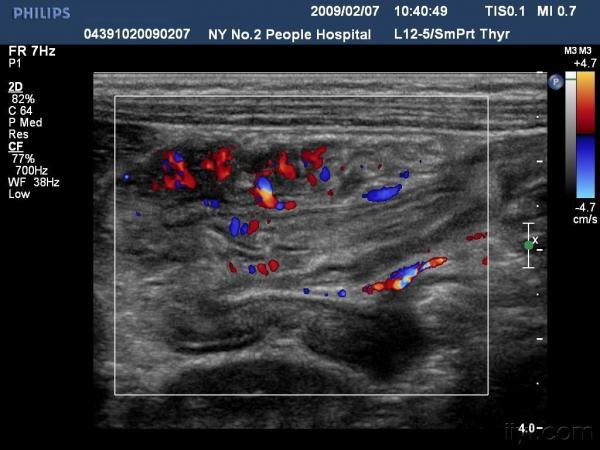

【贴图】肠套叠

患儿哭闹数小时来我院就诊,超声检查发现右侧相当于结肠肝区位置可见“同心圆征”。来和大家分享一下,呵呵。